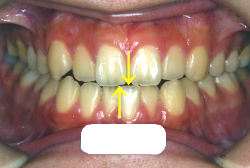

「上の前歯の凸凹」という主訴で来院したケースです。確かに上の左右二番目の歯が内側に引っ込んでいて、凸凹が目立つ状態です。歯並びの凸凹を矯正学では 叢生(そうせい)と言いまして、確かにご本人的にはそこが気になるのですが、矯正学的には前歯の前突の方がより問題となるケースです。

初診時の写真をご覧いただくと、何となく前歯が前傾しているのが感じられると思うのですが、よく見ると上の歯だけでなく、下の前歯も前傾しているのがわかります。このように上の前歯も下の前歯も両方外向きになっている症状のことを、「上下顎前突」と言います。こういうケースの場合は上下左右の小臼歯を抜く(つまり4本抜歯する)ことで配列の中に隙間を作り、その隙間を利用して配列を揃えるだけでなく、 前歯を内側に入れていく治療をします。

治療前後の口元の変化です。前歯の角度が大きく変わりました。治療前は外向きの前歯に押されて、口元がふくらみすぎの状態でした。黄色の線は鼻の頂上と顎の先端を結んだ線で、審美線と言います。審美線と唇はあまり接触しない方が良いと考えられています。矢印の部分がかなりラインオーバーしています。治療後はよりスマートで美しい横顔になりました。このように歯並びを直すと、唇の表情ひいてはお顔全体の表情にも良い変化が生まれます。